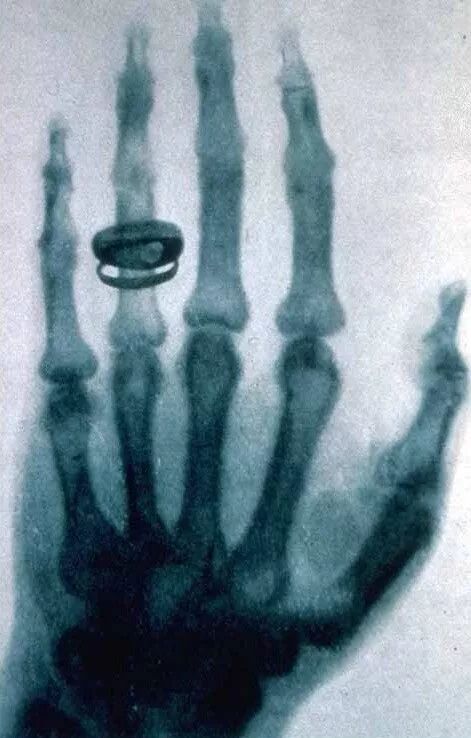

登录/注册后可看大图

伦琴拍摄的一张X射线照片,伦琴夫人的手骨与戒指

20世纪初,人们已经知道了X射线能够穿透人类皮肤和肌肉组织。